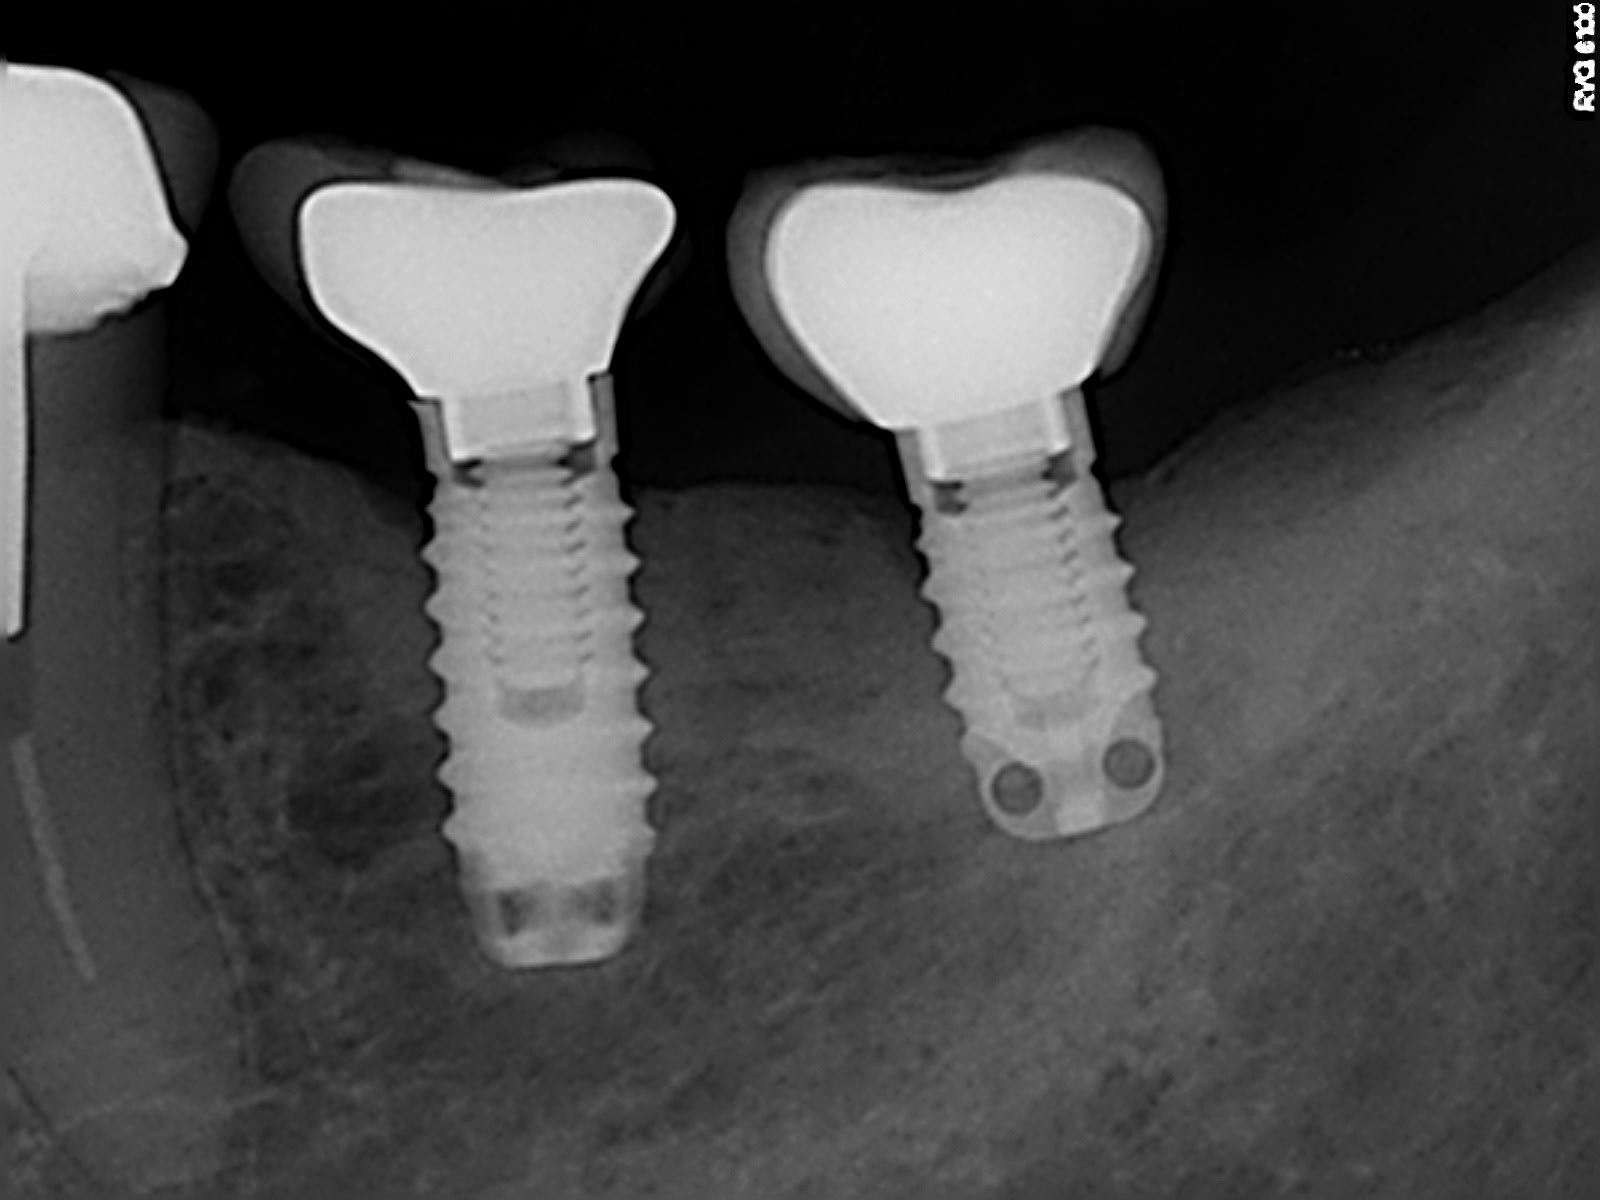

steg

TBR oct in

+1 tbr